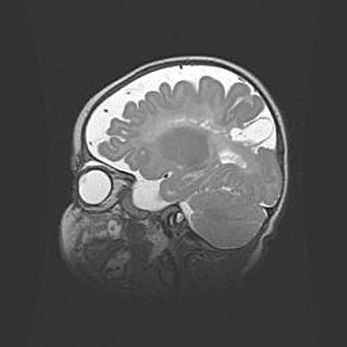

Церебральная ишемия II.

Возраст: 5 дней

Вес: 3400 г

Пол: женский

Окружность головы: 35 см

Срок гестации: 39 недель

Церебральная ишемия – это заболевание, характеризующееся недостаточностью (гипоксией) либо полным прекращением (аноксией) снабжения мозга кислородом по причине закупорки одного или нескольких сосудов. Это приводит к  что метаболическим расстройствам различной степени тяжести в тканях головного мозга, развитию коагуляционных некрозов и гибели нейронов.